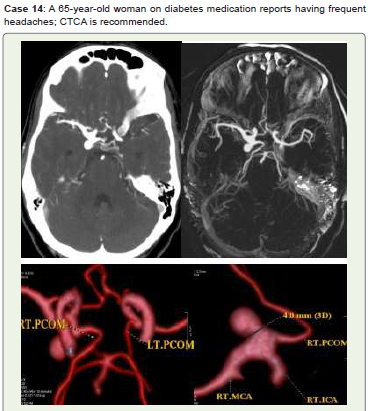

Figure 14:CTCA Axial (A), MIP (B), and 3D-VR images (C, D) show a medium

saccular aneurysm with a neck diameter of 4 mm at the intersection of the right

ICA bifurcation and the origin of the posterior communicating artery (PCOM).

Endovascular therapy and follow-up were recommended for her.